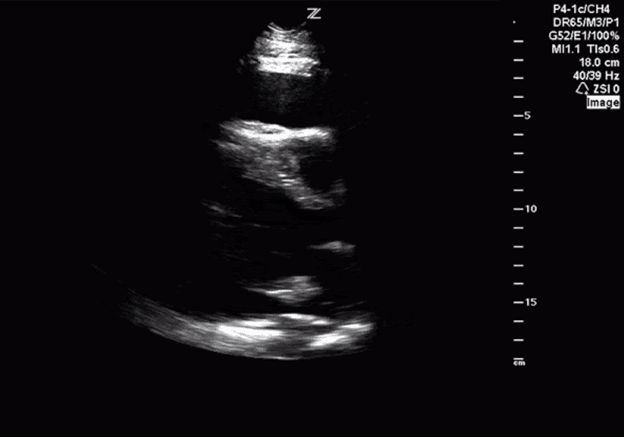

Diese Ansicht ermöglicht die Beurteilung der Funktion des linken Ventrikels, der Symmetrie von Squeeze und der Septumbogenbildung. Der linke Ventrikel ist in dieser Ansicht zu erkennen und erscheint als Kreis unten rechts auf dem Bildschirm. Der rechte Ventrikel erscheint halbmondförmig und befindet sich im oberen rechten Teil des Bildschirms (Bild 7).

PSS-gekennzeichnete Strukturen

Wenn Sie die Sonde zu apikal auffächern und die Herzspitze und nicht die Papillarmuskeln betrachten (Bild 8), erhalten Sie eine falsche Einschätzung der linksventrikulären Funktion.

Schienenbild PSS an Papillarmuskulatur und Apex